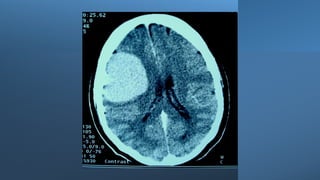

Hemiparesis with facial weakness: brain CT scan or brain MRI, with or

NB: Urgent non-contrast brain CT scan is the most suitable imaging

Paresis, where? Hemiparesis withfacial weakness: brain CT scan or brain MRI, with or without contrast. Hemiparesis without facial weakness: Brain/upper cervical MRI, with or without contrast. NB: Urgent non-contrast brain CT scan is the most suitable imaging modality in patients with acute hemiparesis because of its availability in Emergency Departments (usually), and it is rapid (the period of the test is very brief (compared to MRI). Drawback: poor visualization of posterior fossa structures because of boney artifacts, except in posterior fossa hemorrhages. Paraparesis: dorsal spine MRI, with or without contrast or in some cases, brain/cervical MRI (with or without contrast).